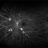

- proliferative diabetic retinopathy (PDR), FA early phase, fluorescein leakage, OPTOS CALIFORNIA, Optos

- Fluorescein Angiogram of a 44 year-old female with PDR.